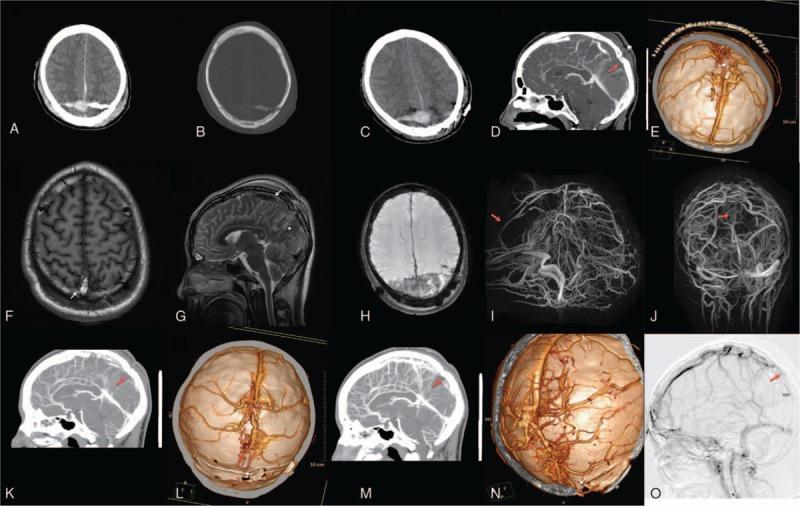

We presented a 22-year-old man with a severe headache and scalp bleeding after a head chop wound. Physical examination identified a 20-cm straight laceration in his parietooccipital scalp. Computed tomography (CT) demonstrated a depressed cranial fracture (DCF) in the left parietooccipital bone, a fracture line across the midline to the right side, and penetrations of bone fragments into the brain parenchyma.

An emergent left parietooccipital craniotomy, followed by cranioplasty to restore the depressed bone flap, was delivered to the patient. Postoperative CT confirmed successful elevation of the DCF and removal of intracerebral bone fragments. However, postoperative CT angiography (CTA) demonstrated an absence of venous flow distal to the fracture, suggesting occlusion of the posterior third of SSS. MRV revealed a persistent absence of venous flow in the posterior third of SSS with dilated cortical venous drainage. Anticoagulation treatment was initiated 3 days after surgery, and follow-up CTA and digital subtraction angiography showed gradually improved patency in the anterior and middle two-thirds of SSS.

The favorable clinical outcome after complete occlusion of the posterior third of the SSS has rarely been reported and it might be explained by our timely surgical intervention and development of compensatory cerebral collateral circulation.